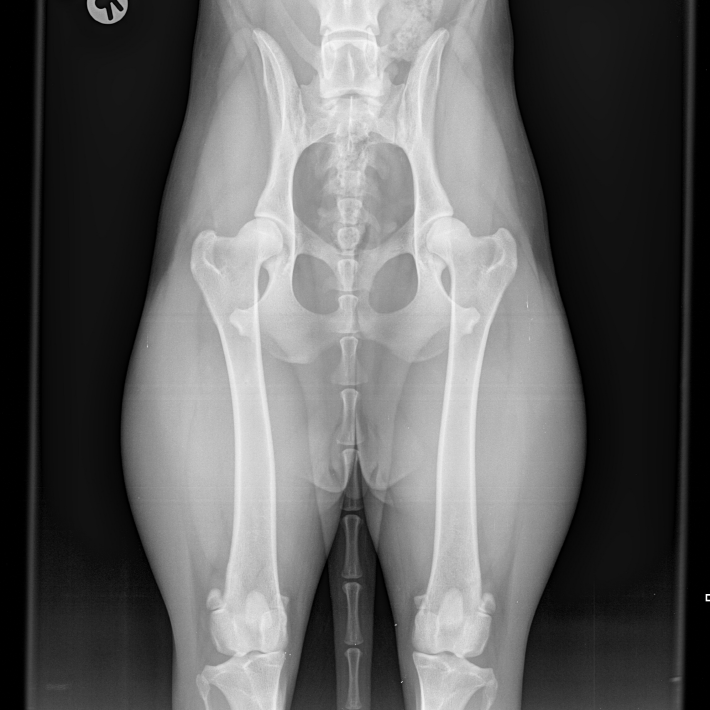

• Formung des Acetabulums: Wie sich die Pfanne unter Belastung entwickelt.

• Femurkopf-Zentrierung: Der entscheidende Faktor der Gelenkentwicklung.

• Biomechanische Ketten: Warum Winkelung, Sprungkraft und Hinterhand zusammenhängen.